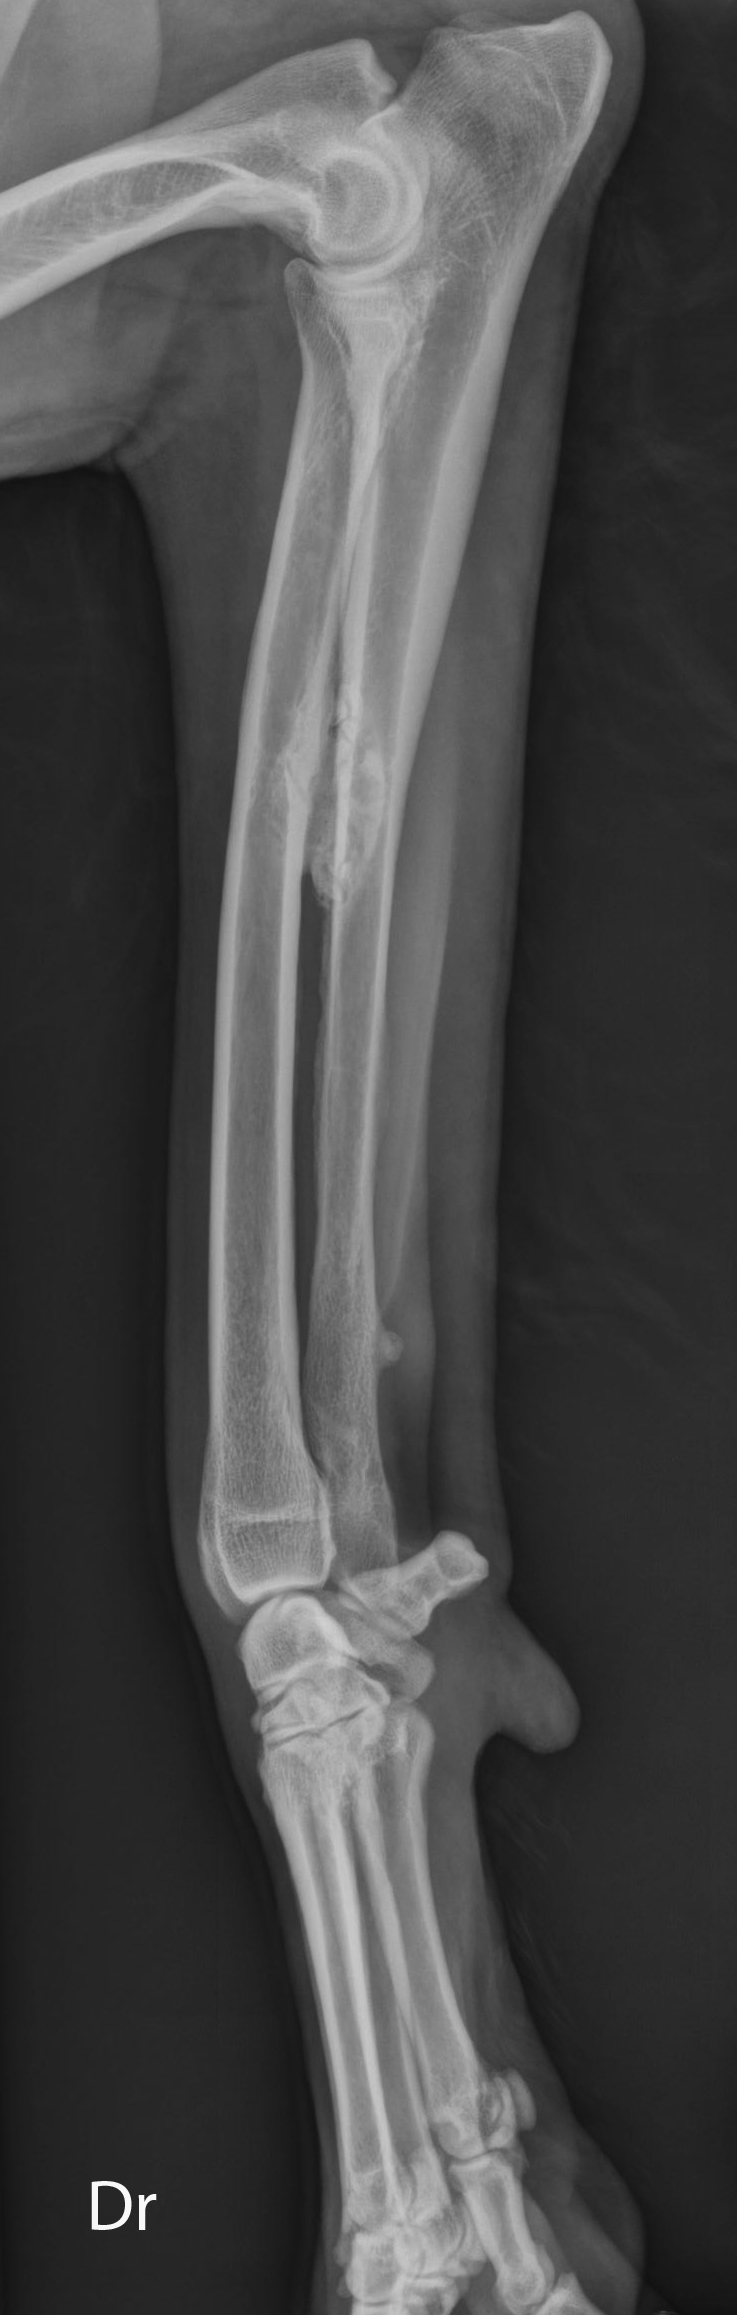

Latérale